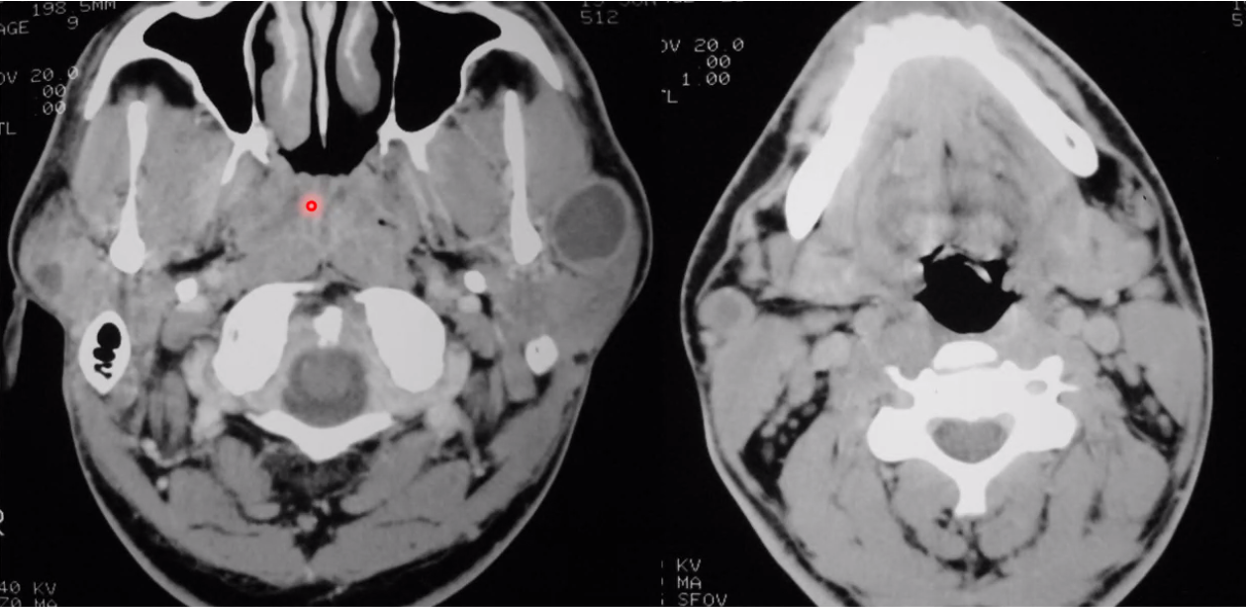

aberrant ICA

lymphoepithelial disease; associated with HIV

LEC typically occurs in patients who are HIV positive. The cysts may be unilateral or bilateral and may be associated with diffuse cervical adenopathy. These patients usually present with a nonpainful enlarging neck mass. It may be difficult to differentiate an intraparotid LEC from an enlarging cervical lymph node based on palpation.

warthin tumors